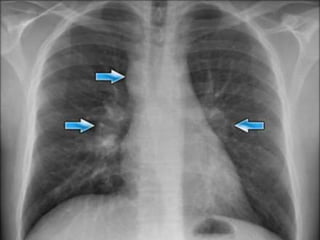

Air Bronchogram

A tubular outline of an airway made visible due to the filling of the surrounding

alveoli by fluid or inflammatory exudates

Conditions in which air bronchograms are seen:

• Lung consolidation

• Pulmonary edema

• Non-obstructive pulmonary atelectasis

• Interstitial disease

• Neoplasm

• Normal expiration

• #10 Bronchi, which are not normally seen, become visible as a result of opacification of the lung parenchyma. Branching, tubular lucencies of bronchi are seen in an opacified lung (Fig. 1a). This sign shows that the pathology is in the lung parenchyma itself (1). This sign is most frequently encountered in pneumonia and pulmonary edema. Its generalized form can be seen in respiratory distress syndrome (2). The air bronchogram sign shows that the central bronchi are not obstructed; however, it can also be seen when a mass causes half-obstruction. Bronchioalveolar carcinoma, lymphoma, interstitial fibrosis, alveolar hemorrhage, fibrosis due to radiation and sarcoidosis can also present with this sign (1–3). This sign can also be seen on CT images (Fig. 1b).